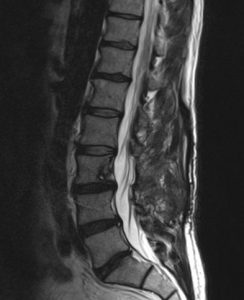

Paciente de 52 años que refiere lumbalgia inespecífica con irradiación ocasional en muslo (justo arriba de la rodilla) derecha. Sin focalidad.

Imagen con gadolinio, distribución homogénea, bordes definidos; la resolución ósea no significa malignidad en estos tumores; la ocupación de canal >50% tampoco significa que sean intradurales subaracnoideos